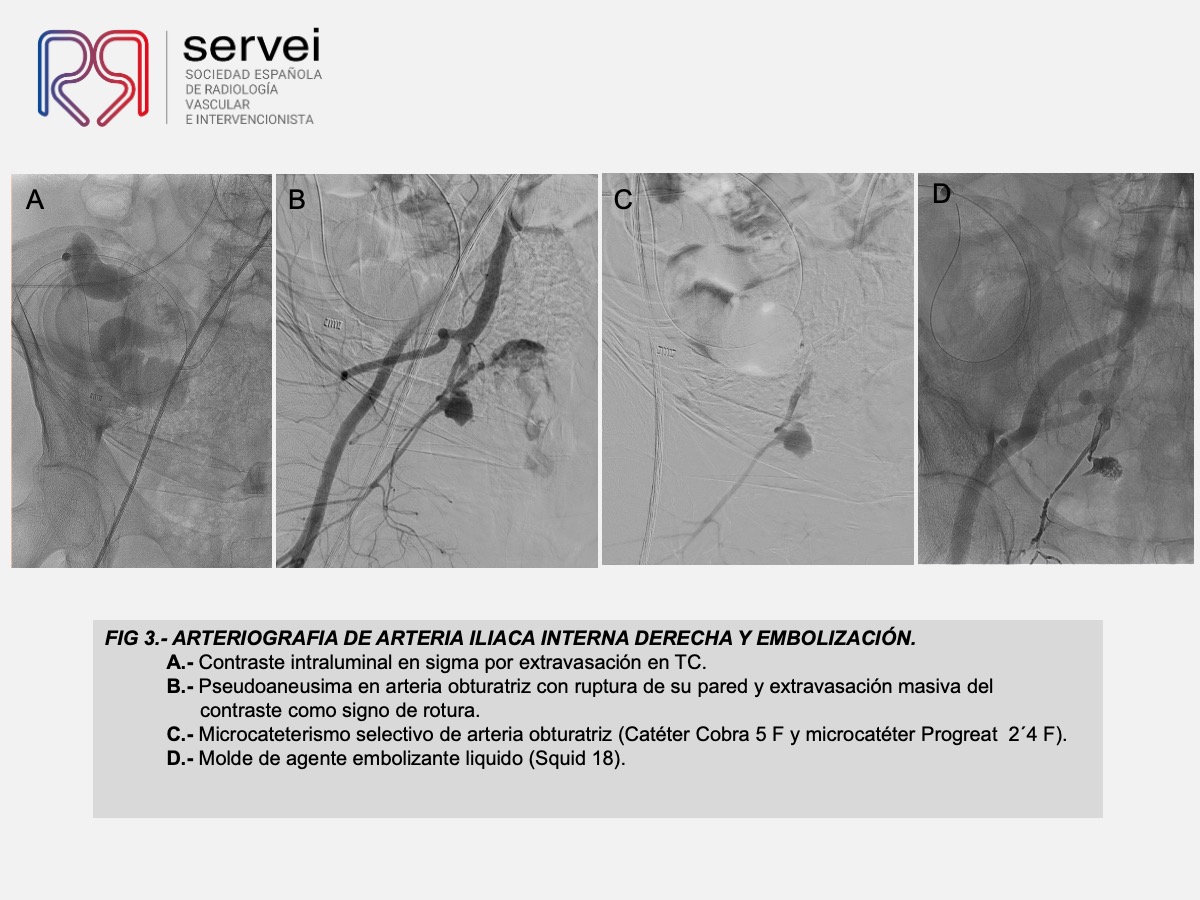

- Pseudoaneurisma arteria obturatriz-rectorragia 01

- Pseudoaneurisma arteria obturatriz-rectorragia 02

- Pseudoaneurisma arteria obturatriz-rectorragia 03

- Pseudoaneurisma arteria obturatriz-rectorragia 04

- Pseudoaneurisma arteria obturatriz-rectorragia 05

- Pseudoaneurisma arteria obturatriz-rectorragia 06

- Pseudoaneurisma arteria obturatriz-rectorragia 07

- Pseudoaneurisma arteria obturatriz-rectorragia 08

- Pseudoaneurisma arteria obturatriz-rectorragia 09